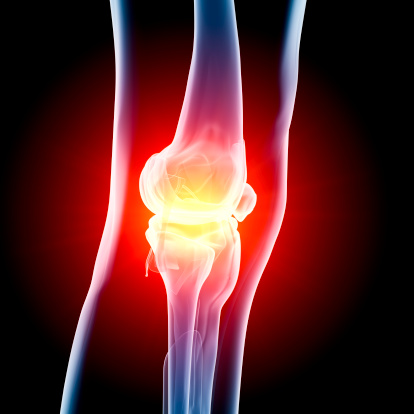

Thousands of people are stricken in the prime of their lives with arthritis; it is not just the elderly that suffer from it. Stiffness, fatigue and widespread muscle aches are the main characteristics of the disease. Sometimes the joint stiffness associated with arthritis can be crippling.

Joint stiffness, joint swelling and pain are common with septic arthritis. The stiffness and other symptoms tend to come on rather quickly so it can be startling to people. It usually attacks just one area or one joint in the body, whereas other forms of arthritis can attack and then spread to various parts of the body. Septic only travels from one joint to the other if it goes untreated for a long period of time.

If you already suffer from arthritis you know how the stiffness and swelling of joints can be debilitating. For some people the stiffness alone makes it difficult to carry out normal activities; even getting dressed can be hard for those who have severe rheumatoid arthritis. Taking precautions like avoiding bad germs in one step towards protecting the human body, another step will be for scientists to find ways to balance that bad bacterium when it does enter our bodies.